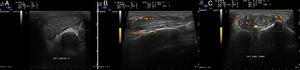

We performed a gray-scale diagnostic ultrasound examination (Esaote MyLab 70®), which showed a round, defined, mobile cluster that extended in a heterogeneous manner throughout the 6 compartments of the extensor mechanism of the wrist (Fig. 2A). Color Doppler ultrasound revealed vascularization corresponding to G3, suggesting an active inflammatory-infectious process (Fig. 2B and C). Ultrasound-guided puncture yielded 5cc of cloudy fluid that, in direct Gram stain, showed abundant leukocytes, the absence of microorganisms and aerobic culture was negative. Ziehl–Neelsen stain disclosed no acid-fast bacilli either. However, after 9 days in Lowenstein–Jensen culture at 37°C, the existence of Mycobacterium tuberculosis was confirmed. A chest radiograph revealed a cardiothoracic index >0.5, sternal cerclage, minimal posterior strangulation of the costophrenic sinus, increase in right apical density, and tuberculostatic treatment was begun with 5 drugs (5 tablets of Rimstar®/day, together with oral vitamin B6/weekly, for 9 months), to treat infectious monoarthritis produced by M. tuberculosis.

(A) Image of the dorsal compartment of right wrist. Distortion of the architecture of the extensor compartments. Presence of a large soft tissue mass that deforms the border of the common extensors, the extensor of the fifth finger and the extensor of the ulna. (B) Longitudinal view, and (C) transverse view of the common extensor tendon of the fingers at the level of the wrist. Increase in neovascularization with evident color Doppler signal (G3) showing activity over the extensor tendon and infiltration of surrounding infectious material.